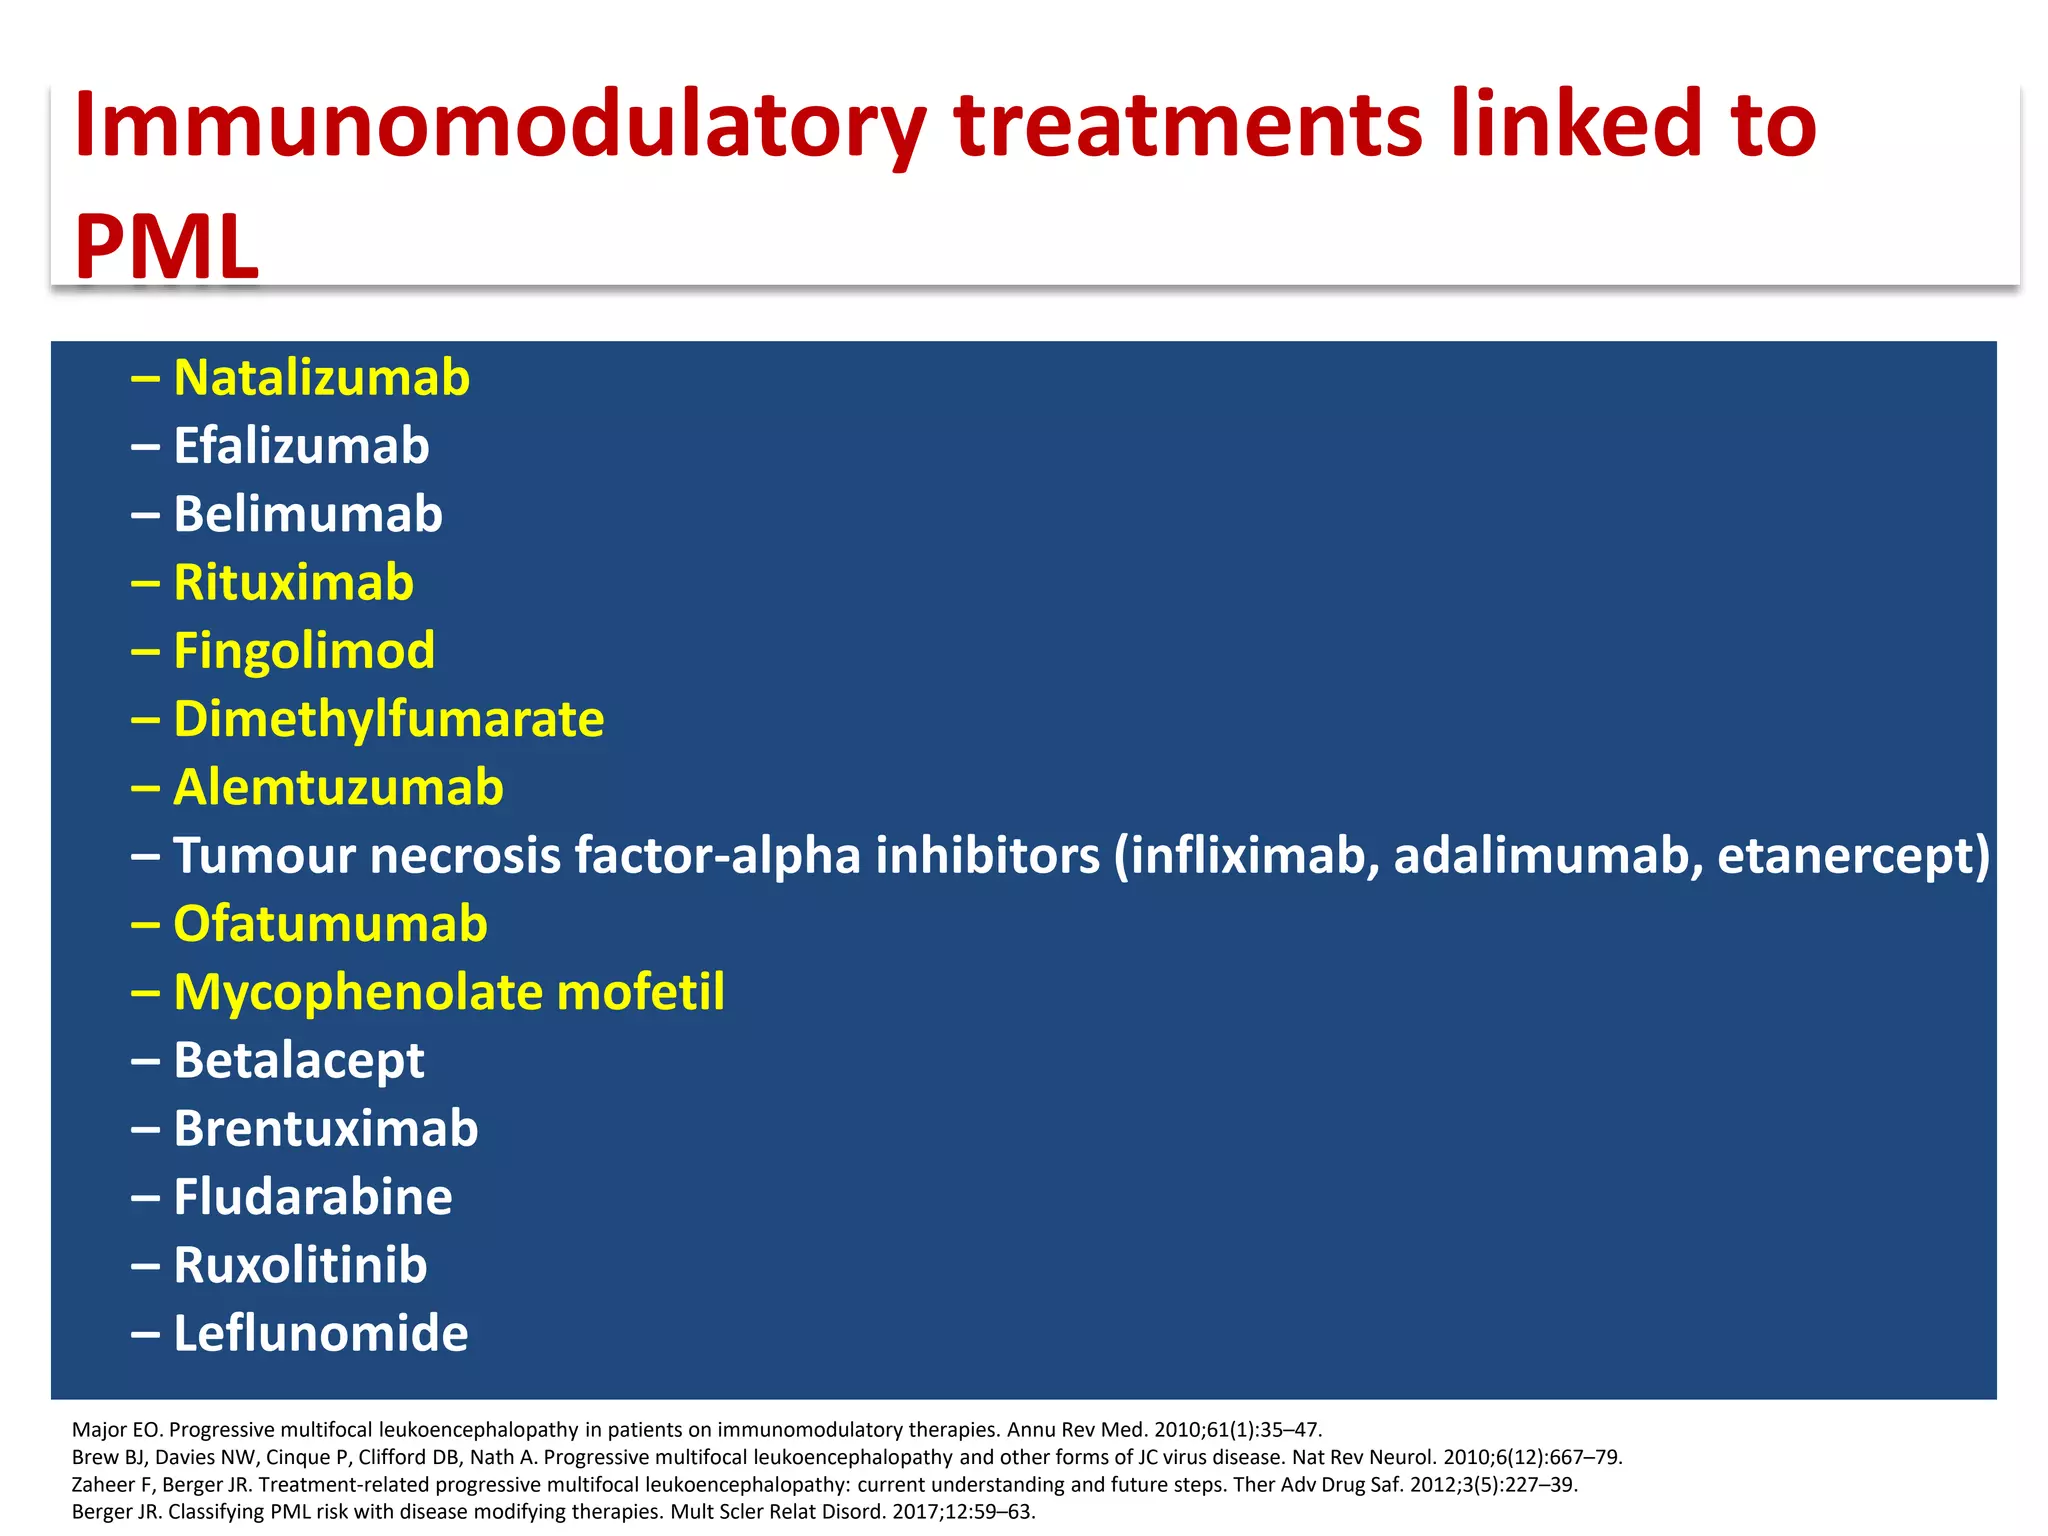

This document discusses progressive multifocal leukoencephalopathy (PML), an opportunistic infection caused by the John Cunningham virus (JCV) that leads to demyelination in the central nervous system. It highlights the epidemiology, clinical manifestations, diagnostic methods, and risk factors associated with PML, particularly in immunocompromised patients and those undergoing immunomodulatory therapies. It also presents data on the incidence of PML in patients treated with natalizumab and other therapies, addressing the relationships between these treatments and the development of PML.